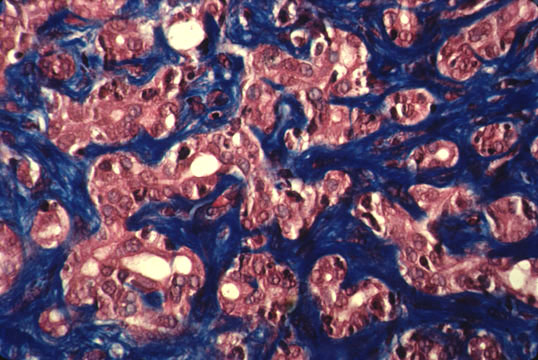

Biliary fibrosis

Fig.74 - BILIARY FIBROSIS: Concentric peribiliary fibrosis with some inflammatory cells in a case of ascending cholangitis.